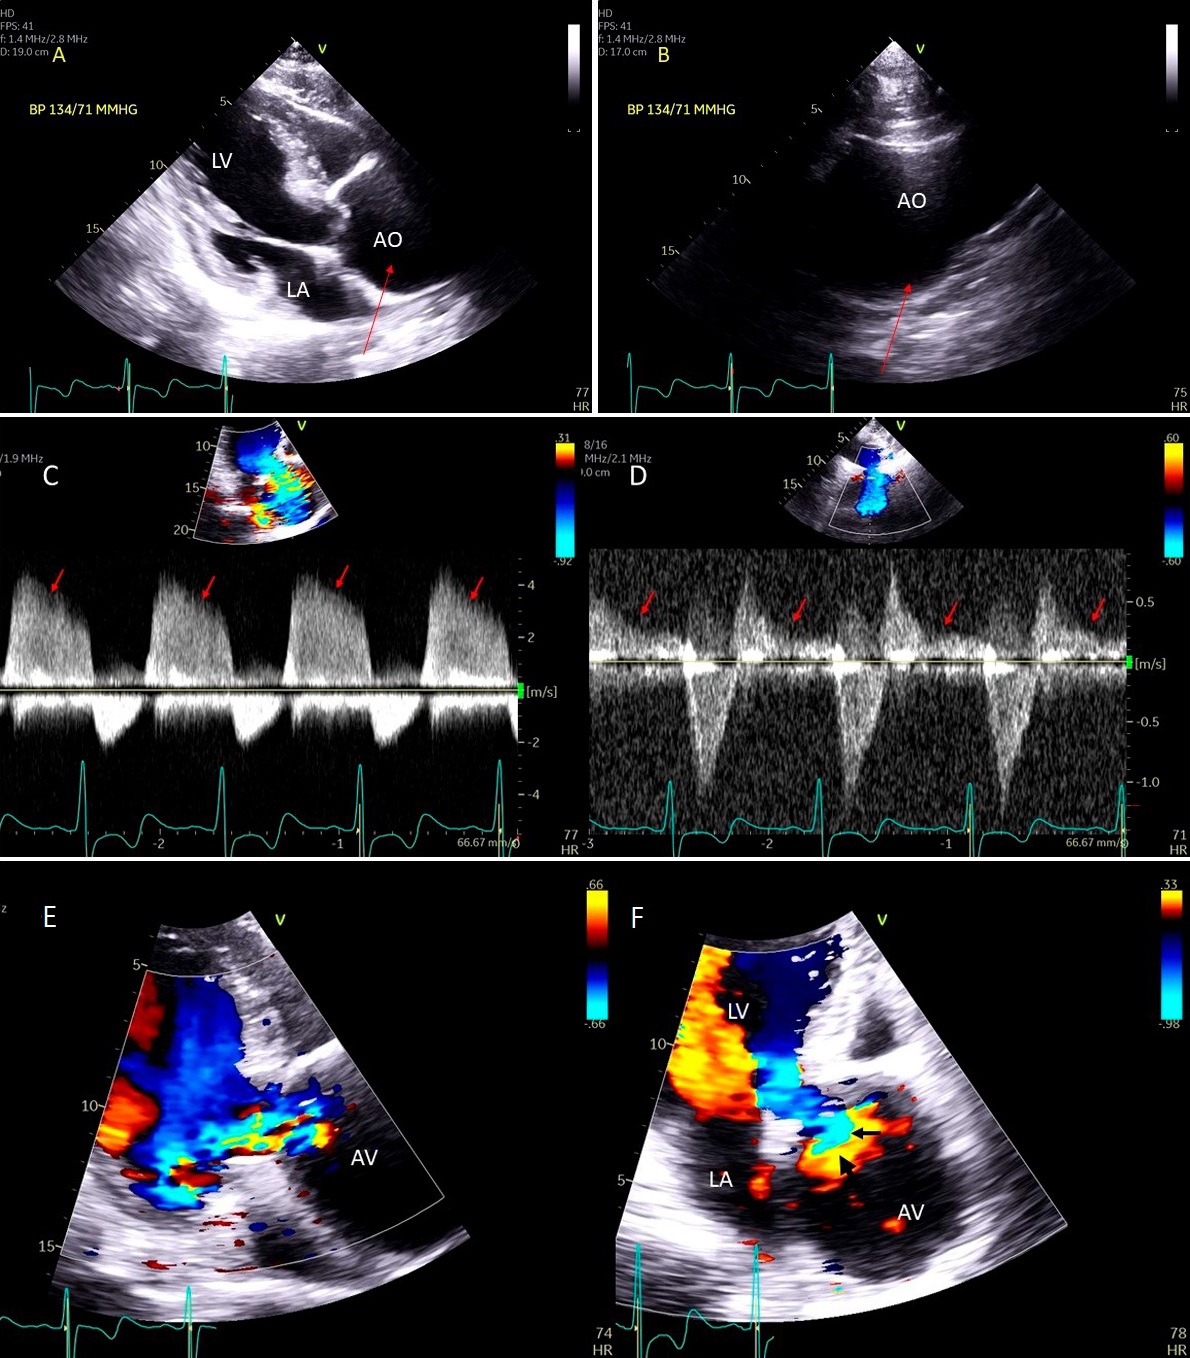

Fig. 9.Aortic valve regurgitation induced by dilated annulus. (A)

Transthoracic echocardiogram parasternal long axis view showing

markedly dilated aortic sinuses (red arrow). (B) Imaging at a higher parasternal window shows aneurysmal aortic sinuses (red arrow)

and normal ascending aorta above sinotubular junction.

(C) Three chamber view with continuous-wave (CW) Doppler showing dense AI Doppler

envelope with a steep deceleration slope (red arrows) suggesting severe AI. (D) CW Doppler recording at the proximal descending thoracic aorta

demonstrating pandiastolic flow reversal (red arrows), another feature of severe AI.

(E) Color Doppler parasternal long axis view showing AI color

jet occupying two third of the LV outflow tract with a wide vena contracta at origin from the aortic valve leaflets (

Common causes of leaflet malfunction causing AR include degenerative leaflet calcifications, and infective endocarditis (Fig. 10), bicuspid aortic valve perforation and rheumatic fever. The causes of AR include Marfan’s syndrome, annulo-aortic ectasia (idiopathic root dilatation) (Fig. 9), aortic dissection, connective tissue disease, and syphilis. The Carpentier classification is also widely used to describe the mechanism of AR [63].